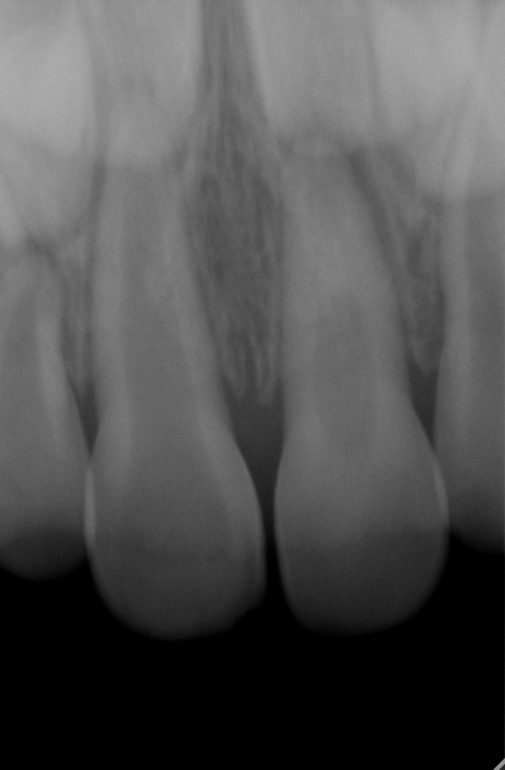

Здравствуйте!Подскажите пожалуйста что делать?Ребенок упал 6 марта этого года и дарился о железную ограду,было много крови и подвижность зубов.Также верхняя губа вздулась и и стала в 3 раза больше чем нижняя, сильная гематома.При походе к нашему врачу сказали,что пока мазать гепариновой мазью,но через два дня верхнюю губу пришлось вскрыть и наложить дренаж,т.к.было сильное уплотнение.По истечении 1,5 недель я увидела что два передних центральных зуба приобрели более серый оттенок по сравнению с другими, преимущественно в верхней части,где десна.Врач сказал что нужно удалять пульпу с нервами и что зуб уже не восстановится.Примечательно еще то что у нас ровно год назад тоже была травма,также припухла губа,но не было гематомы и зуб пострадал верхний левый центральный, который через две недели посерел и тоже говорили,что он таким и останется по цвету, но через полтора месяца он восстановился и по цвету не отличается от других зубов.Вчера 27 марта мы были у другого стоматолога и без снимком, а просто осмотрев зубы (т.к. снимки у нас в электронном виде на почте) он сказал, что правый центральный верхний зуб нужно полностью удалять,т.к. он уже и мертвый,между губой и десной образовался свищ и удалять просто нерв, а сам зуб оставить черевато может быть тем,что инфекция может остаться в корне зуба и и повлиять на коренной зуб.А если удалить полностью, то мы исключим это.Могу прикрепить снимки,которые были сделаны в тот же день,6 марта,после удара.Что вы можете сказать,очень важно ваше мнение тоже?Заранее огромное спасибо!